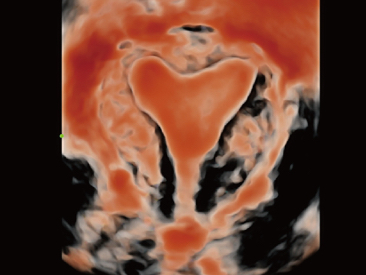

Oltre alla qualit├Ā delle immagini di livello eccellente, Resona 7 migliora anche le capacit├Ā di ricerca clinica il rivoluzionario V Flow per la valutazione emodinamica vascolare, e l'acquisizione piani pi├╣ intelligente dal set di dati 3D per la diagnosi del sistema nervoso centrale fetale. Combinando il pi├╣ intuitivo funzionamento multi-touch basato su gesti e tutte le caratteristiche cliniche essenziali, Resona 7 sta veramente portando nuove tendenze nellŌĆÖinnovazione dellŌĆÖecografia.